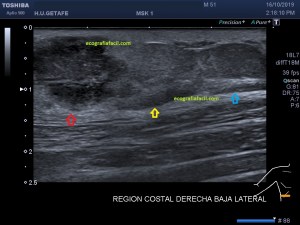

En la imagen 3 ves una imagen de un lipoma, mide 7 cms, la huella de la sonda mide 5cms, la «panoramic view» posee una regla centimetrada que sigue el contorno de la imagen, justo en la profundidad de la misma y lo marca la flecha amarilla. La profundidad la marca la flecha roja y la flecha blanca marca el rango centimetral de los 5cms, fíjate que la línea blanca es ligeramente mayor cada 5 cms. Sirve de referencia, como en la imagen 4 donde ves una colección en el glúteo de más de 10 cms.